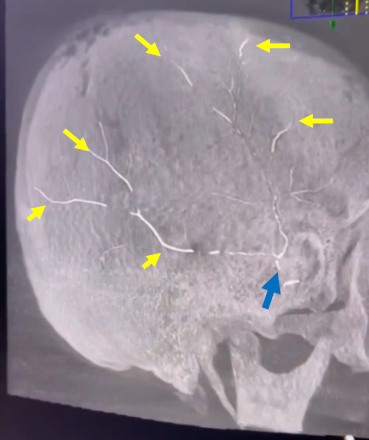

Next-Generation Liquid Embolic, NeoCastTM, Successfully Occludes Distal Middle Meningeal Artery Branches of Chronic Subdural Hematoma Patients in Initial Cohort of First-In-Human Study

Abstract Body: Introduction: NeoCast is a novel, solvent-free, non-adhesive, shear-thinning, liquid embolic agent designed to reproducibly achieve distal penetration of the microvasculature. In preclinical models NeoCast showed deeper and more consistent distal penetration relative to commercial benchmarks. These properties were confirmed in the EMBO-01 clinical study which demonstrated initial safety, excellent embolic performance, and extensive tumor devascularization in patients with hypervascular extra-axial tumors. Here, we report on the first use of NeoCast for MMA embolization in an initial cohort of patients with chronic subdural hematomas (cSDH) from the EMBO-02 study.

Results: An initial cohort of patients (age range: 55-80 years old) was enrolled in EMBO-02 including one patient presenting with a bilateral hematoma. All target MMA vessels were successfully embolized with NeoCast (volume injected: average 0.22ml, range 0.06-0.43ml) resulting in complete occlusion with no non-target embolization. Injection occurred in both flow-directed (placed proximal to bifurcation) and wedge position (selected distal branch) scenarios. In both scenarios, deep distal penetration was achieved with embolic reaching the falx. The investigator was satisfied to very satisfied with NeoCast’s overall embolization performance as graded on the usability questionnaire. No device-related serious adverse events have been reported to date.